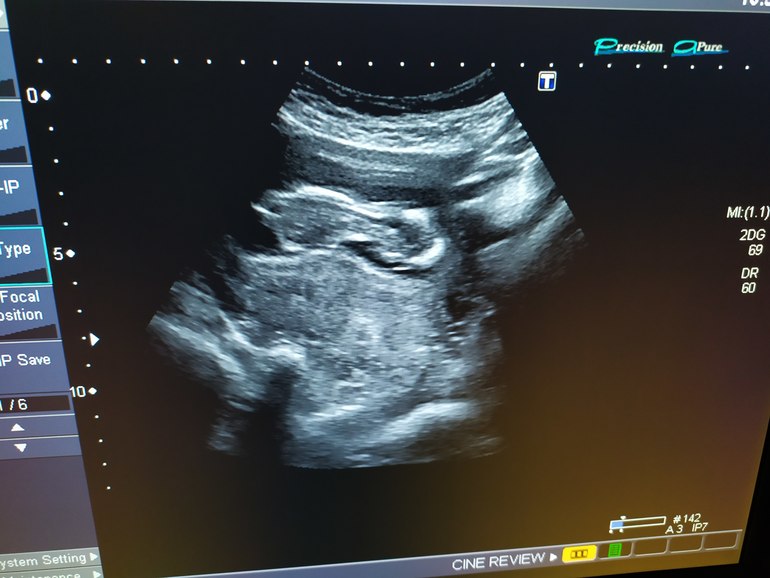

И меня отпустило☺В 7 недель позвонила доктору, которой очень доверяю, спросила когда на УЗИ и по смотреться. Она сказала, что на УЗИ когда первый скрининг, а смотреться пока незачем - не нужно, чтобы лишний раз растущее зëрнышко кто-то тревожил(обожаю еë😍) Так и доходили до 10 недель. На 10 неделе решила стать на учëт, но по мнению гинеколога ЖК "жаль, что не подтвердила беременность на УЗИ" Дала направление на скрининг и на учëт не поставила😅Ну и ладно. Скрининг прошли через 2 недели. И вот так наша кукла решила показаться))) всей своей спиной😄